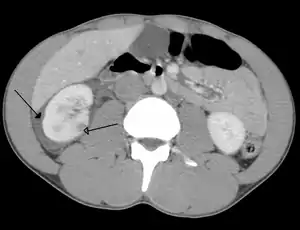

Spleen

Spleen is the most common cause of massive bleeding in blunt abdominal trauma to a solid organ. Spleen is the most commonly injured organ. A laceration of the spleen may be associated with hematoma.[13] Because of the spleen's ability to bleed profusely, a ruptured spleen can be life-threatening, resulting in shock. However, unlike the liver, penetrating trauma to the spleen, pancreas and kidneys do not present as much of an immediate threat of shock unless they lacerate a major blood vessel supplying the organs, such as the renal artery.[5] Fractures of the left lower ribs are associated with spleen lacerations in 20 percent of cases.[9]